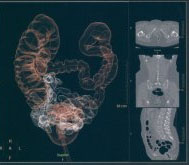

Метод неинвазивного исследования толстого кишечника, основанный на его визуализации с использованием возможностей современной рентгеновской мультиспиральной компьютерной томографии. Это особый вид компьютерной томографии, при которой исследуется толстая кишка. Обычная колоноскопия (не виртуальная) - это эндоскопический метод диагностики, при котором эндоскоп вводится в кишку непосредственно.

Исследования проводятся на компьютерном томографе Toshiba AQUILION 128 срезов с применением газового инсуфлятора Ulrich Medical